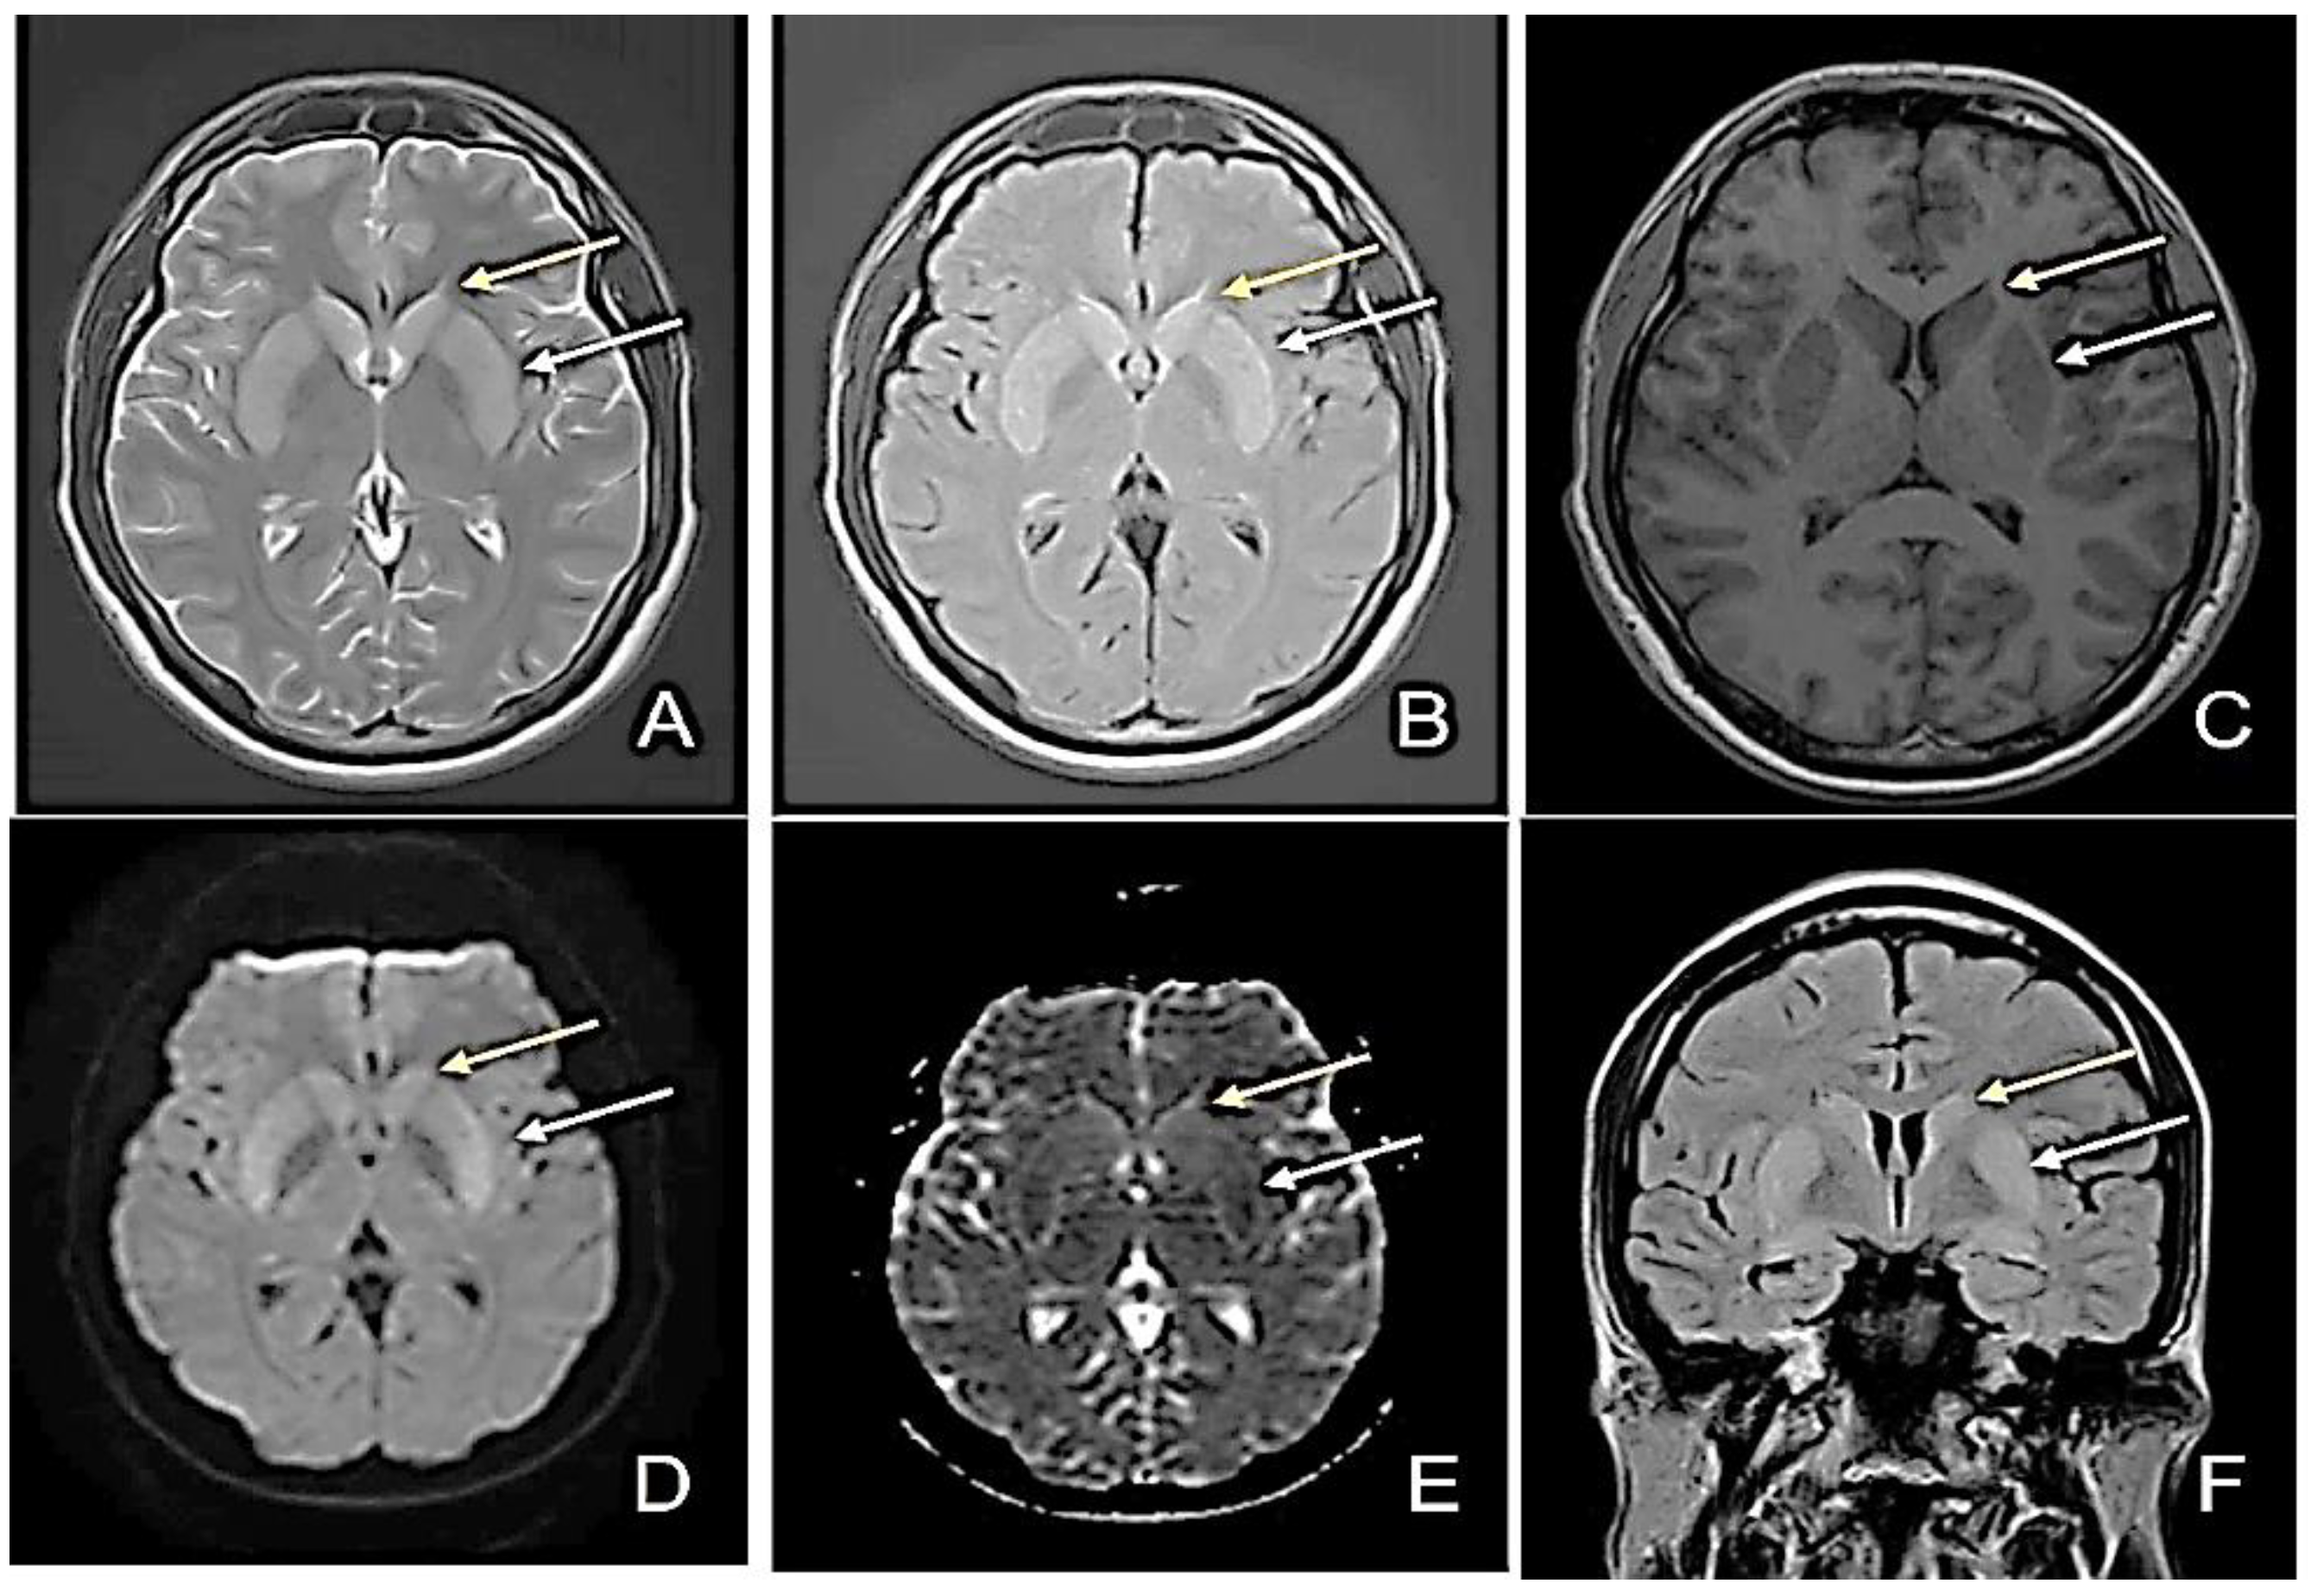

MRI Evolution of a Patient with Viral Tick-Borne Encephalitis and Polymorphic Seizures